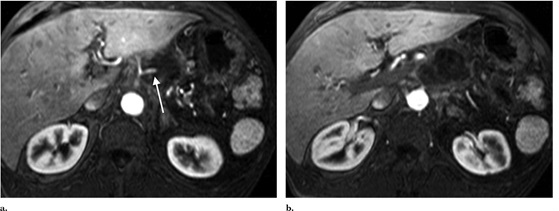

在随后两周的随访中,病人出现轻微间歇性疼痛,没有出现疲劳,发烧或其他症状。每次消融后24小时之内都使用对比增强磁共振成像(图3),第二次消融后的30天预期消融区没有出现增强。消融区的脉管系统尤其是脾动脉和肠系统上动脉保持明显不变的术前外表。血清肿瘤抗原在消融手术后30天从1500U/mL减少到404U/mL90天达到407U/mL。诊断后使用PET/CT成像(图4)如图所示出现了一个轻微的氟脱氧葡萄糖周边圈。虽然没有观测到参与肿瘤或节似疾病,但是在治疗后的三个月PET/CT扫描出了1.5cm的肝转移。因病变远离大血管在经皮RF消融后肝转移被成功治愈,然后开始吉西他滨化疗。RF消融两个月,诊断后六个月,磁共振成像显示腹部没有疾病恶化或复发。癌症病源19-9水平六个月减少到236U/mL。

MR image at 1 month after IRE procedure. (a) Superior aspect of tumor shows no residual enhancement of tumor, with maintained patency and appearance of the splenic artery (arrow). (b) At the level of the superior mesenteric artery, complete necrosis is also seen.